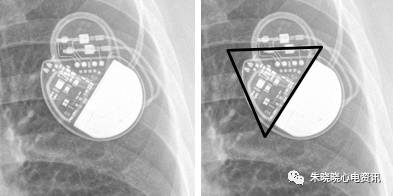

百多力起搏器看起来像鸟嘴(图5)

图5 百多力起搏器

美敦力的Vitatron起搏器除外电池其余部分呈三角形(图7),

图7 美敦力公司Vitatron起搏器